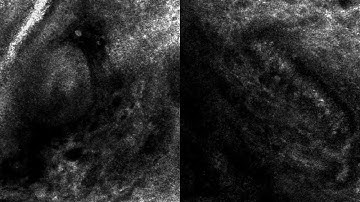

Radial Video Captured Using Reflectance Confocal Microscopy